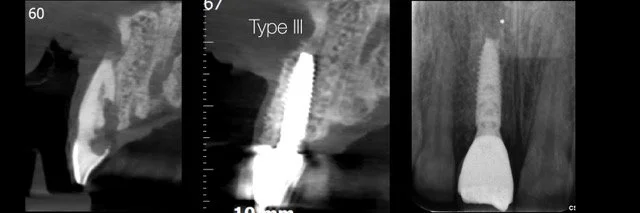

• Atsevišķi zobu implanti estētiskajā zonā

• Implanta dizaina un savienojuma, abatmentu izvēles un ārstēšanas procesa nozīme

• Transmukozālās kontūras veidošana ap implantiem: izpratne, dizains un klīniskā pieeja

• Tūlītēja, agrīna, atlikta vai vēlīna implantācija?

• No audu saglabāšanas līdz tūlītējās slogošanas protokoliem

16.00 - 18.00 | Tūlītēja implanta ievietošana estētiskajā zonā (#21) un mīksto audu pārvaldība; Digitāli vadīta tūlītēja implanta ievietošana zoba vietā nr. 12 ar horizontālu GBR un CTG, izmantojot diska perforācijas (disc-punch) kaula transplantācijas tehniku. (praktiskās nodarbības Proimplant apmācību telpā Türi 10C Tallinā)